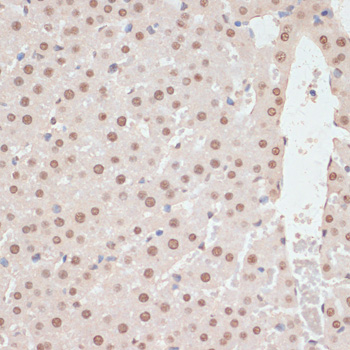

AMP-activated protein kinase (AMPK), an important serine/threonine protein kinase that plays a key role in coordinating metabolism and energy. It is the core to studying diabetes and other metabolic diseases. AMPK is expressed in a variety of metabolic-related organs and can be activated by various stimuli including cellular stress, exercise, and many hormones and substances that affect cell metabolism. AMPK proteins from different species all exist in the form of a heterotrimer complex consisting of an α-catalytic subunit, a β-regulatory subunit, and a γ-regulatory subunit.